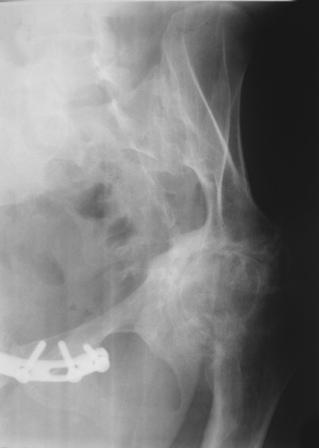

Уважаемые коллеги! Пациентка 32 года с застарелым повреждением таза, после остеосинеза лонного сочленения пластиной. Посоветуйте с выбором тактики и методик лечения.

Получила травму в феврале 2004г в г.Лобытнанги ЯНАО Тюм.обл. Через неделю после поступления выполнен остеосинтез лонного сочленения пластиной. 1,5 месяца на скелетном вытяжении. В последующем ходит при помощи костылей с нагрузкой на правую ногу. Имеется нестабильность половин таза, неправильно-консолидированный перелом левой вертлужной впадины, невропатия седалищного нерва слева. В результате невропатии седалищного нерва сформировалась эквинусная установка левой стопы,парестезии по подошвенной поверхности.

Направлена к нам для устранения патологической установки стопы и эндопротезирования левого тазобедренного сустава, также имеется миграция шурупов пластины, фиксирующей лонное сочленение.

Клинически: ходит на костылях с нагрузкой на правую ногу. Левая стопа в эквинусе. Осевая нагрузка на левую н\конечность болезненна в области левого тазобедренного сустава, при прикосновениях к подошвенной поверхности стопы у пациентки чувство зжения. В левом коленном суставе полный обьем движений, в левом тазобедренном резко ограничено отведение и ротация, укорочение левой н\конечности на 2,5 см. При полипроекционной и функциональной Р-графии выявлена нестабильность левого КПС и лонного сочленения, консолидированный в порочном положении поперечный оскольчатый перелом левой вертлужной впадины с центральным смещением головки бедра. Нами выполнена коррекция деформации левой стопы. Планируется выполнить введение 2 канюлированных илиосакральных винтов слева, реостеосинтез лонного сочленения реконструктивной пластиной, после заживления ран - тотальное эндопротезирование левого тазобедренного сустава.